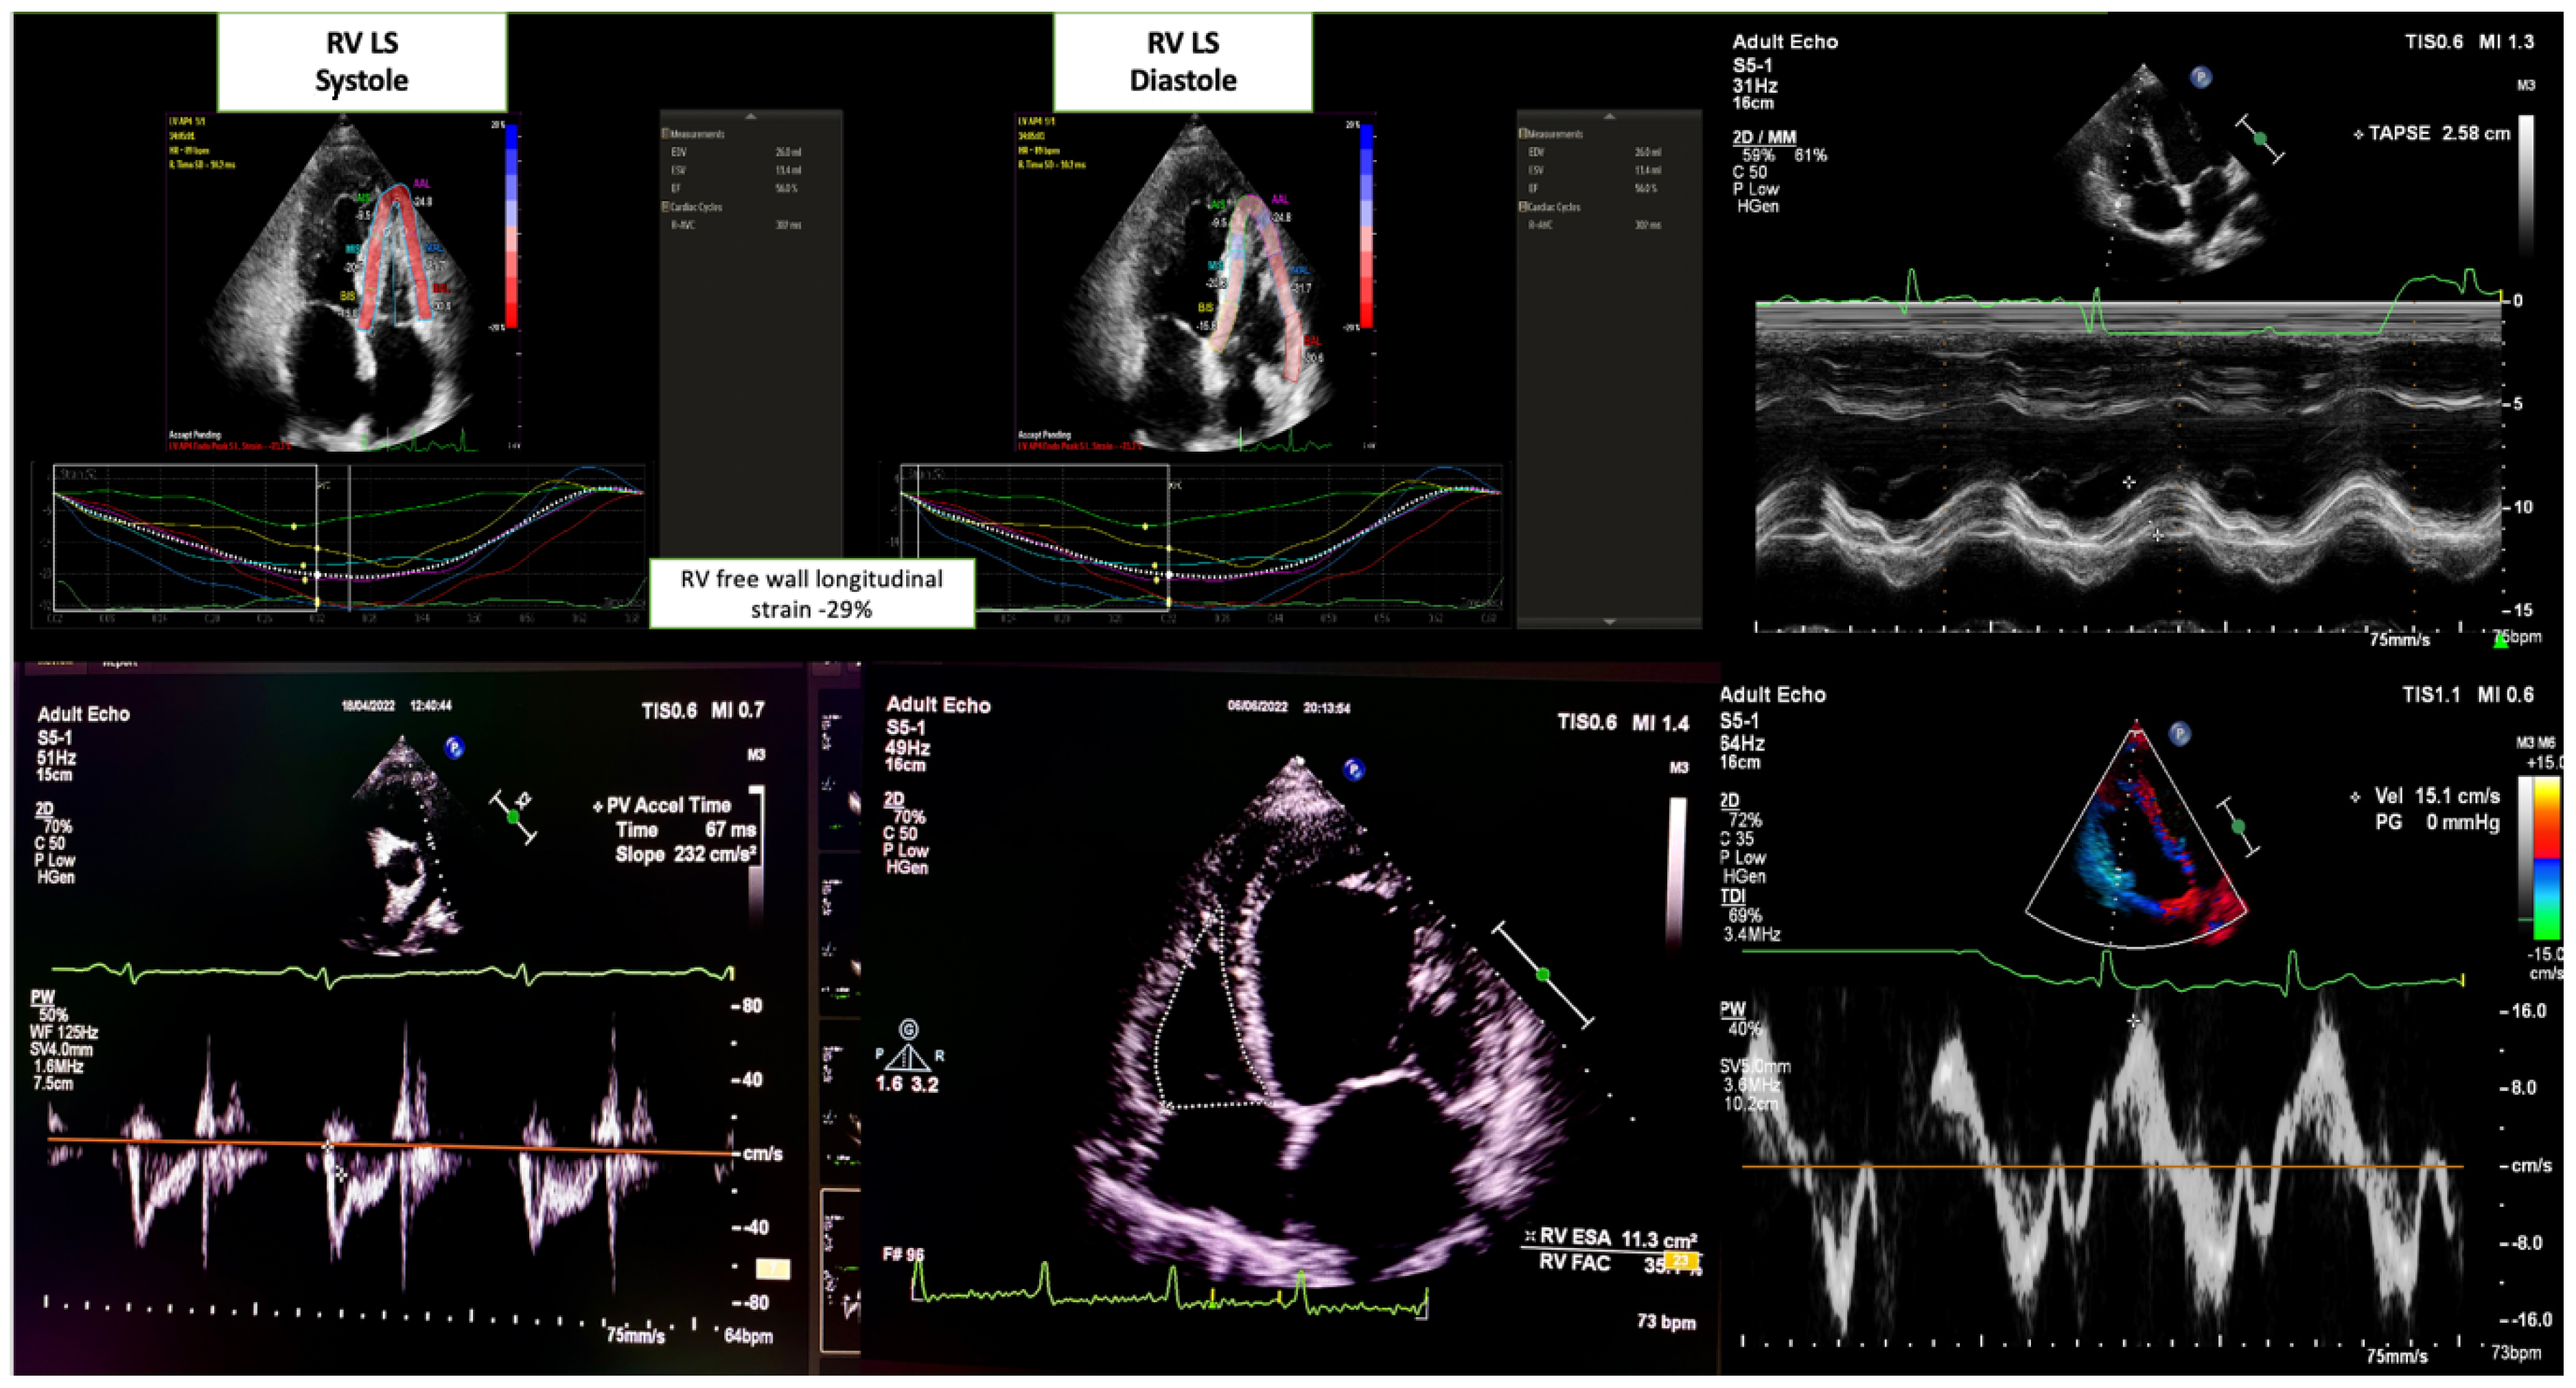

- RV systolic function: Evaluated using the apical four-chamber view. The key parameters were as follows:

- Tricuspid annular plane systolic excursion (TAPSE) measured via M-mode.

- Peak systolic tricuspid annular velocity (RV TDI S′) was obtained using tissue Doppler imaging.

- RV fractional area change (RV FAC) was calculated as the percentage of RV end-diastolic and end-systolic area changes.

- Pulmonary valve: Assessed using continuous wave (CW) and pulsed wave (PW) Doppler on the parasternal short axis. Pulmonary acceleration time was measured using PW Doppler across the pulmonary valve.